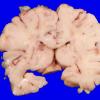

Menkes disease (4)